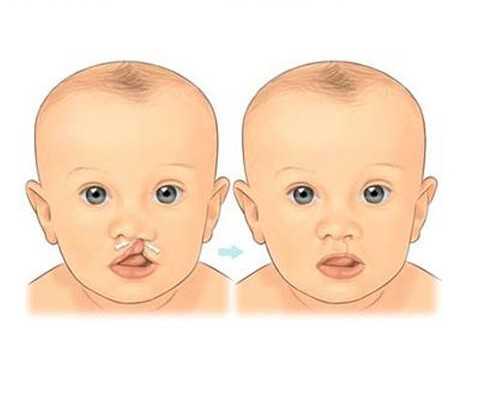

四、代孕協(xié)議的替代方案

考慮到代孕協(xié)議的非法性和風(fēng)險(xiǎn),建議代孕人和受孕方尋求其他替代方案,如領(lǐng)養(yǎng)、試管嬰兒等。這些方案都是合法的,可以有效地解決生育難題。同時(shí),政府和社會(huì)也應(yīng)該加強(qiáng)對(duì)代孕行業(yè)的監(jiān)管和管理,保護(hù)代孕人和受孕方的合法權(quán)益。

總之,代孕協(xié)議是一項(xiàng)非法行為,存在巨大的風(fēng)險(xiǎn)和不確定性。代孕人和受孕方應(yīng)該選擇其他替代方案,同時(shí)政府和社會(huì)也應(yīng)該加強(qiáng)對(duì)代孕行業(yè)的監(jiān)管和管理,以保障代孕人和受孕方的合法權(quán)益。